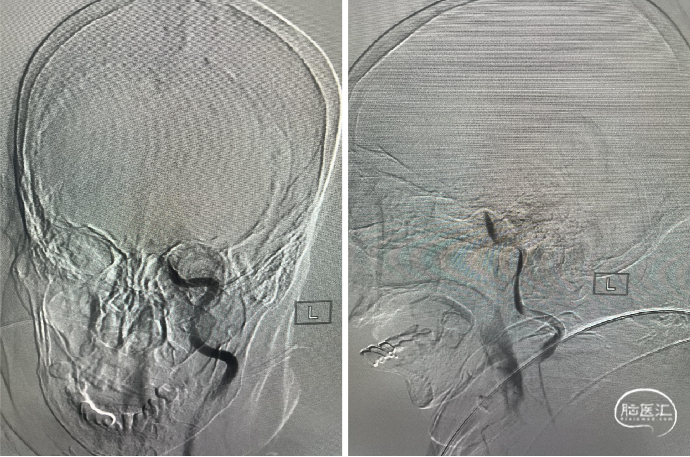

DSA:左侧颈内动脉C4段闭塞。

侧支循环评估:

DSA:通过左侧大脑前动脉软膜支、左侧大脑后动脉软膜支少量代偿。

建立通路:

泥鳅导丝(150cm 0.035″)携带5F多功能导管将8F导引导管送至左侧颈总动脉近颈内动脉起始处,6F远端通路导管超选左侧颈内动脉,送至左侧颈内动脉虹吸段,跟进8F导引导管至C1中段。